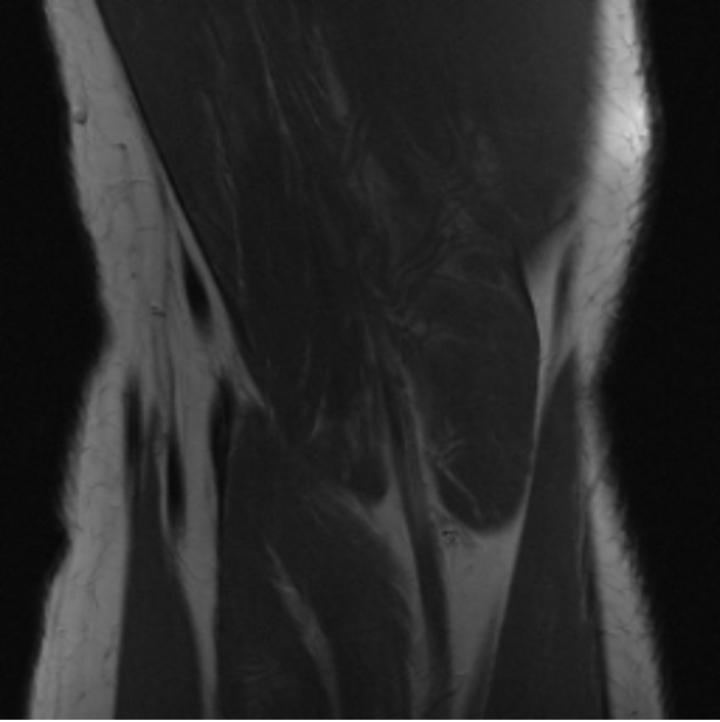

One way to test the generalization capability of the trained X-Diffusion is to test it on a completely different domain from an MRI dataset not seen during training. We report the single-slice results on the test set of knees from NYU fastMRI [33, 80], using the X-Diffusion trained on the BRATS brain MRIs. The test PSNR result is 34.17 and an example is shown in Figure 8. It shows how successfully X-Diffusion can generate knee MRIs (out-of-domain) despite being trained on brains.

Small Knee MRIs clinical study. To qualitatively assess how realistic our generated knee out-of-domain 3D volumes were (produced from a single slice), we gave 20 generated examples alongside their real MRI counterparts to an expert orthopedic surgeon J. F.. He was then asked to identify the real example from a set of 20 MRI pairs. The surgeon correctly identified the real MRI in only 10 out of 20 pairs, could not decide in 3 pairs, and misidentified the generated MRI as real in the remaining 7 pairs. This further validates the generated out-of-domain MRIs.